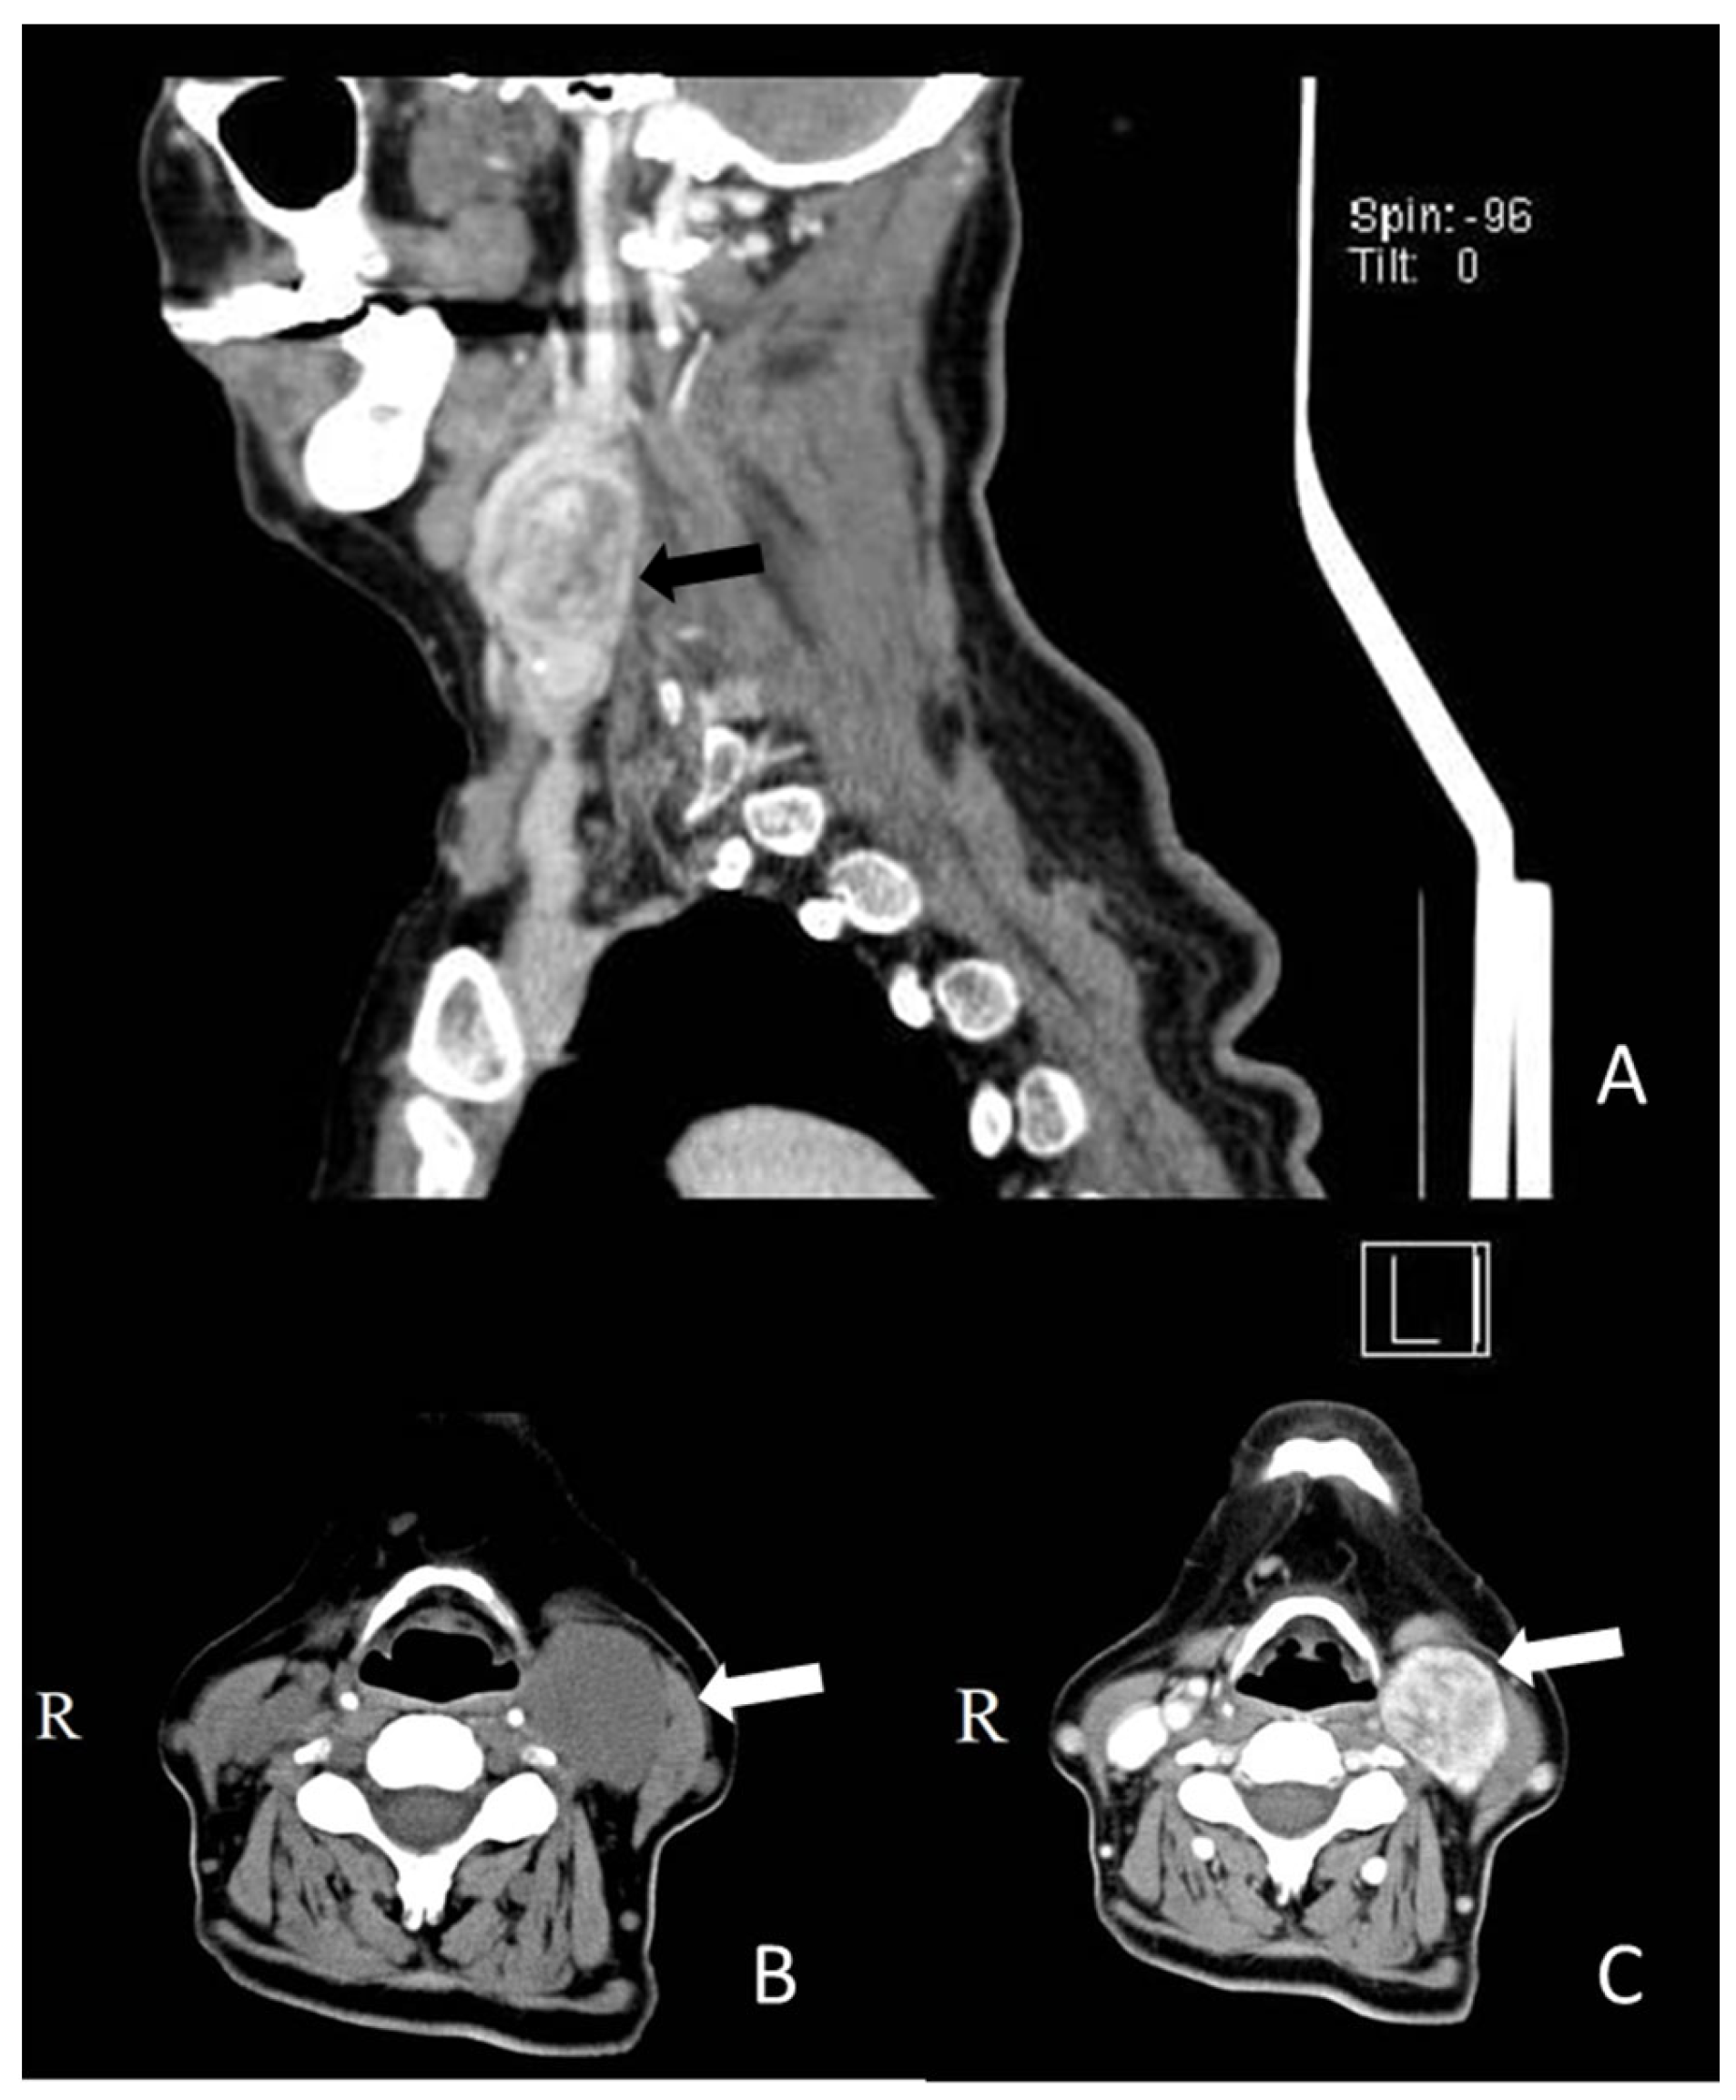

2. Case Report